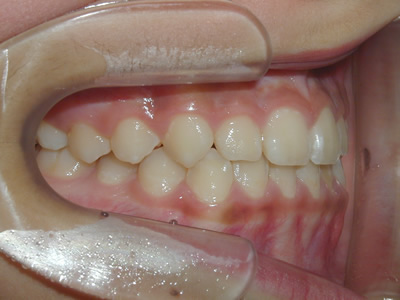

永久歯に交換するためのスペース不足による前歯のガタガタで、取り外しができる拡大床にて上下顎の幅を拡大した後、上顎の前歯をマルチブラケット装置で並べました。治療の期間は1年9か月でした。

終了時